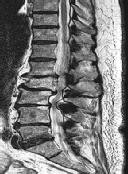

CLINICAL SITUATION

Figures 1 and 2 are the sagittal and axial MRI images at the L4-5 level from a patient with intractable left leg pain, paresthesias, and weakness of grade 3

of 5. Physical therapy has failed, and the patient feels he is becoming progressively weaker.

Discussion: C

The MRI images show a left L4-5 posterolateral disk herniation compressing the left L5 nerve root. Posterolateral disk herniations in the lumbar spine affect the traversing nerve roots; therefore, at the L4-5 level, the traversing L5 nerve would be affected. Far-lateral disk herniations in the lumbar spine affect the exiting nerve roots, so a far-lateral herniation at L5-S1 would affect the L5 nerve root also. The motor innervation for the lumbar nerve roots are L2: hip flexion, L3: knee extension, L4: ankle dorsiflexion, L5: long toe extension, and S1: ankle plantar flexion. The sensory innervation for the lumbar nerve roots are L3: medial thigh, L4: anterolateral thigh and medial calf, L5: anterolateral calf, and S1: lateral foot. Nonsurgical treatment, including medications and physical therapy, has failed, and the patient has noticed a progressive deficit confirmed by weakness of grade 3 of 5 on examination. Surgery is indicated because of the patient’s progressive weakness and the failure of nonsurgical care. A fusion is not indicated without evidence of instability.